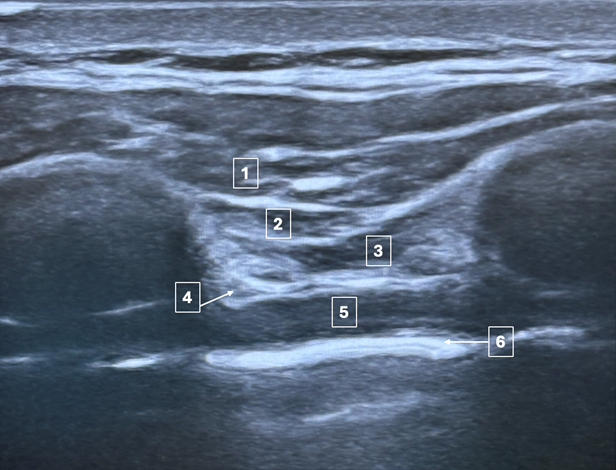

A 10-year-old with bicuspid aortic valve presents for a Ross procedure. They are consented for a deep parasternal intercostal plane (DPIP) block. What is the correct order of anatomical structures in the ultrasound image below, from superficial to deep (1 to 6)?

The deep parasternal intercostal plane (DPIP) block is a regional technique used to provide analgesia to the anterior chest wall. This block targets the anterior branches of the intercostal nerves (T2-T6) as they course anterior to the internal mammary vasculature. Local anesthetic is deposited into the fascial layer between the internal intercostal muscle and the transversus thoracic muscle1,2. As local anesthetic is injected, these layers are separated, as illustrated in Figure 1.

Figure 1: Image A: The needle is seen traversing the tissue layers prior to injection of local anesthetic. Note the location of the pleura (arrow). Image B: Following injection, the anesthetic spreads and separates the tissue layers, displacing the pleura inferiorly.

The correct answer is A – the layers depicted in the picture from superficial to deep are the pectoralis major, external intercostal muscle, internal intercostal muscle, transversus thoracic muscle, internal mammary artery, and the pleura.